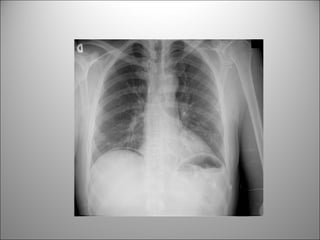

SOSPECHA DE PERFORACIÓN

PUEDE DETECTAR AIRE LIBRE EN CÚPULAS

DIAFRAGMÁTICAS

*** MUCHO MAS SENSIBLE LA PLACA DE TORAX***